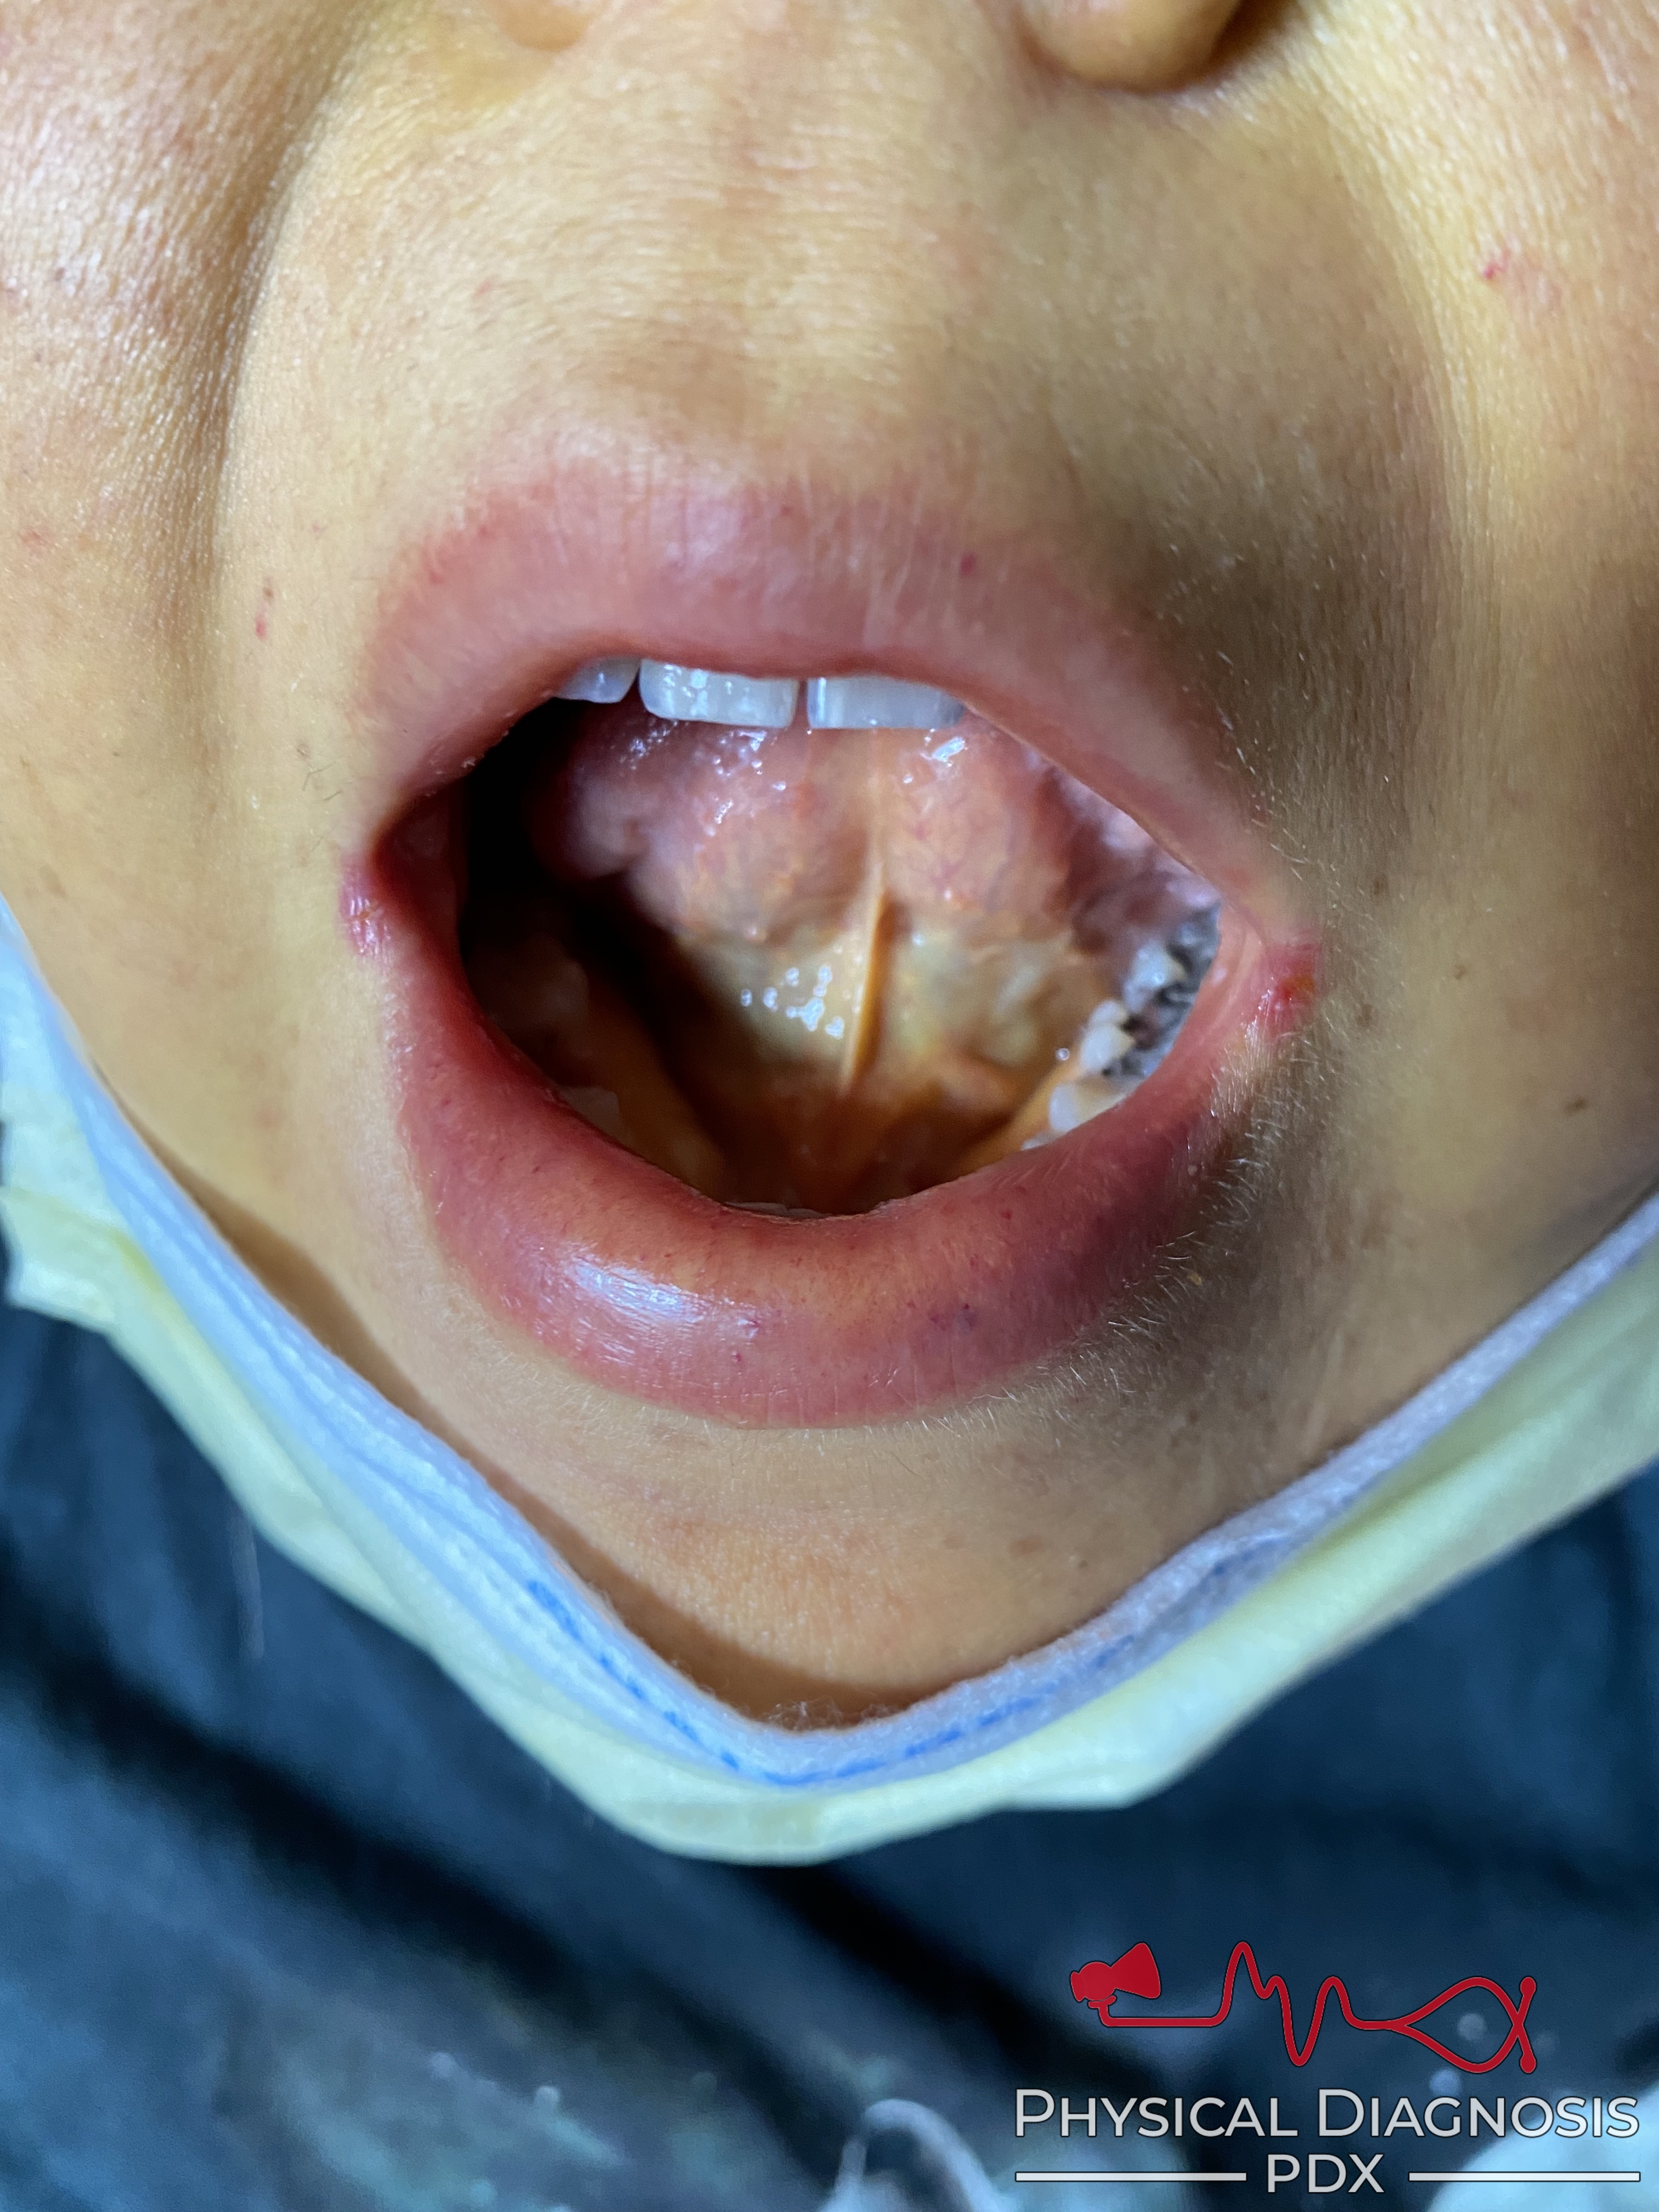

Patient 2:

This is a young woman with severe alcoholic hepatitis.